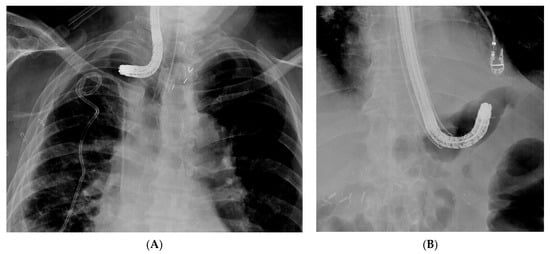

5.1. Pre-Procedure Difficulties

5.2. Intra-Procedure Difficulties

5.3. Post-Procedure Difficulties